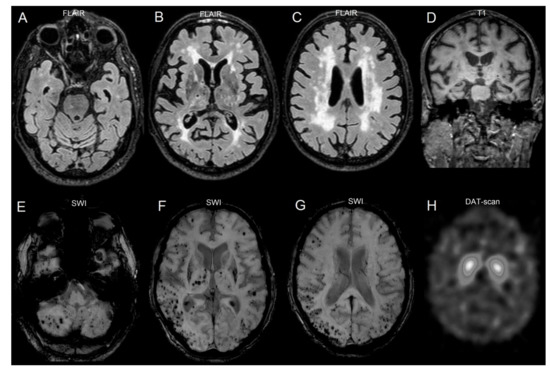

3.2. Neuroimaging